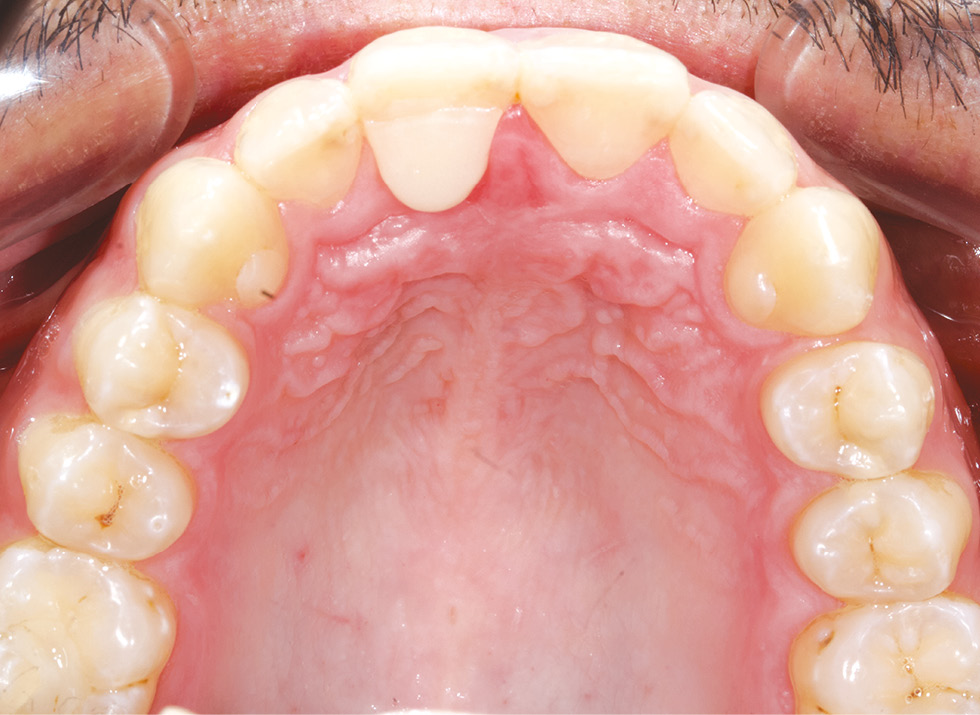

Затем накладки, имитирующие увеличенный объем коронки, были фрезерованы на аппарате CoriTech 350 (Германия) и фиксированы в полости рта испытуемых на зуб 1.1 с помощью жидкотекучего композитного материала Filtek Ultimate Flowable Restorative (3M ESPE) по стандартному протоколу (рис. 8–10).

Рис. 10. Накладка на зубе 1.1

Fig. 10. Overlay fixed on tooth 1.1.